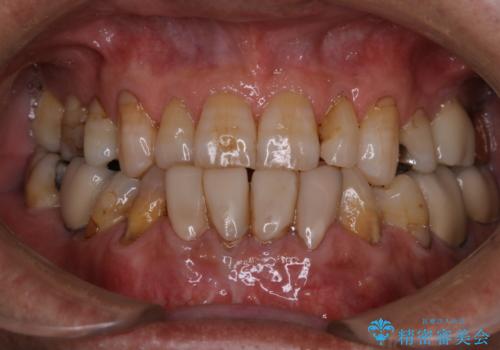

久しぶりのPMTCでメンテナンス

- 忙しくて、しばらくクリーニングをしていないため、全体的にしっかりとクリーニングしてほしいとのことでした。PMTC60分コースを行いました。